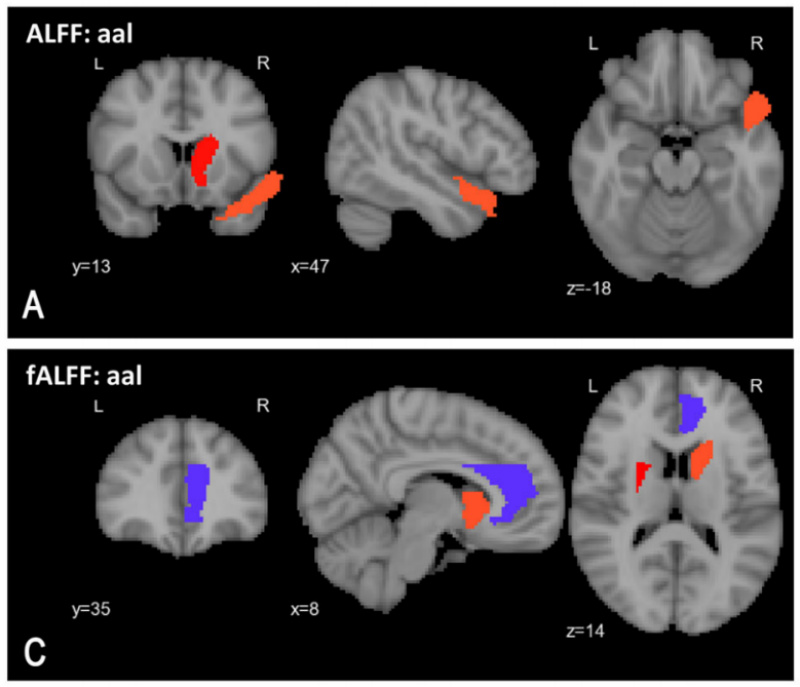

The result is EMPaSchiz (Ensemble algorithm with Multiple Parcellations for Schizophrenia prediction), a model that has been trained on scans from many patients diagnosed with schizophrenia.

When put to the test, EMPaSchiz was able to identify the disease in new scans with 87 per cent accuracy, outperforming existing AI models in identifying the disease.